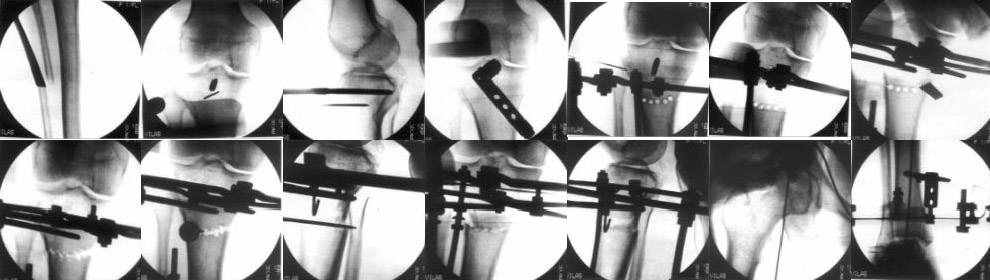

I do upper tibial osteotomies with either an ilizarov fixator and acute correction of the deformity or with an orthofix with gradual correction.

Sending you pics of the steps of the osteotomy and the frame.

You can do the osteotomy in a "focal dome" or in a transverse fashion. The dome has the advantage of having a good contact, allowing weight bearing as tolerated early on.

The level is below the tibial tuberosity.

The frame I use is pretty simple, with one wire each in the proximal and distal ring, two schanz pins in the proximal ring, and one each in the middle and distal ring.

I preconstruct a frame with the proximal ring in varus by the use of coupled washers in the threaded rods in the front and back. These are used as hinges, and after the correction, a medial and lateral threaded rod is also added.

Since the center of rotation of these deformities is usually near the knee joint line, lateral translation of the distal fragment is necessary to normalise all the axes.

You can also do the osteotomy in a transverse fashion.

When I use an orthofix fixator, the osteotomy is oblique, starting below the tuberosity and ending 1 cm away from the lateral cortex at the level of the head of the fibula. No fibular osteotomy is needed there. The deformity is gradually corrected over 2 or three weeks.

You could also do the same with an ilizarov fixator